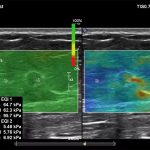

Imagini clinice:

Aplicatii: